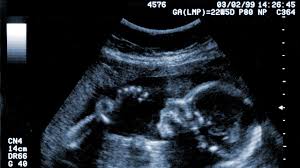

Could what you eat during pregnancy literally change how your baby’s face develops? It sounds almost unbelievable, but research shows that your prenatal diet actually shapes your child’s facial structure, breathing ability, and lifelong health.

The Critical Window: Weeks 6-9 of Pregnancy

Here’s what every pregnant woman needs to know: weeks 6-9 of pregnancy are make-or-break for your baby’s facial development. During this tiny window, vitamin K2 plays a starring role.

Without enough K2, researchers found something alarming: the nasal septum (that’s the cartilage in your nose) calcifies too early. This causes the middle of the face and upper jaw to be underdeveloped, leading to: